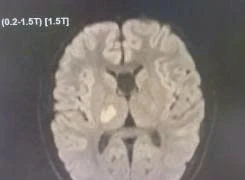

Tiêu sợi huyết cứu bệnh nhân đột quỵ giờ thứ 2

Thuốc tiêu sợi huyết chỉ có hiệu quả tối ưu trong vòng 4 giờ đầu kể từ khi khởi phát triệu chứng. Mỗi phút trôi qua là hàng triệu tế bào não bị mất đi.